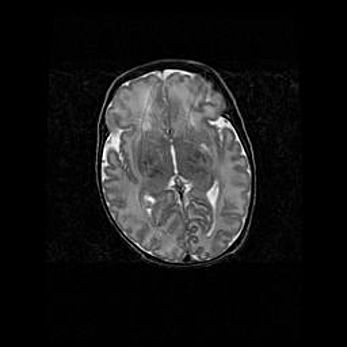

Лейкомаляция с кистозно-глиозной дегенерацией головного мозга.

Возраст: 2 месяца 25 дней

Вес: 6400 г

Окружность головы: 40 см

Срок гестации: 41 неделя

Лейкомаляцию относят к ишемически-гипоксическим повреждениям головного мозга, диагностируемым у новорожденных. При лейкомаляции в головном мозге обнаруживают очаги некроза, возникшие после тяжелой гипоксии и нарушения кровотока. В процессе морфогенеза очаги проходят три стадии: 1) развития некроза, 2) резорбции и 3) формирования глиозного рубца или кисты. Перивентрикулярная лейкомаляция (ПЛ) встречается примерно в 12% случаев среди новорожденных, обычно – у недоношенных детей, причем, частота ее зависит от массы, с которой младенец появился на свет. Наибольшее число малышей страдает лейкомаляцией, если масса при рождении 1500-2500 г.